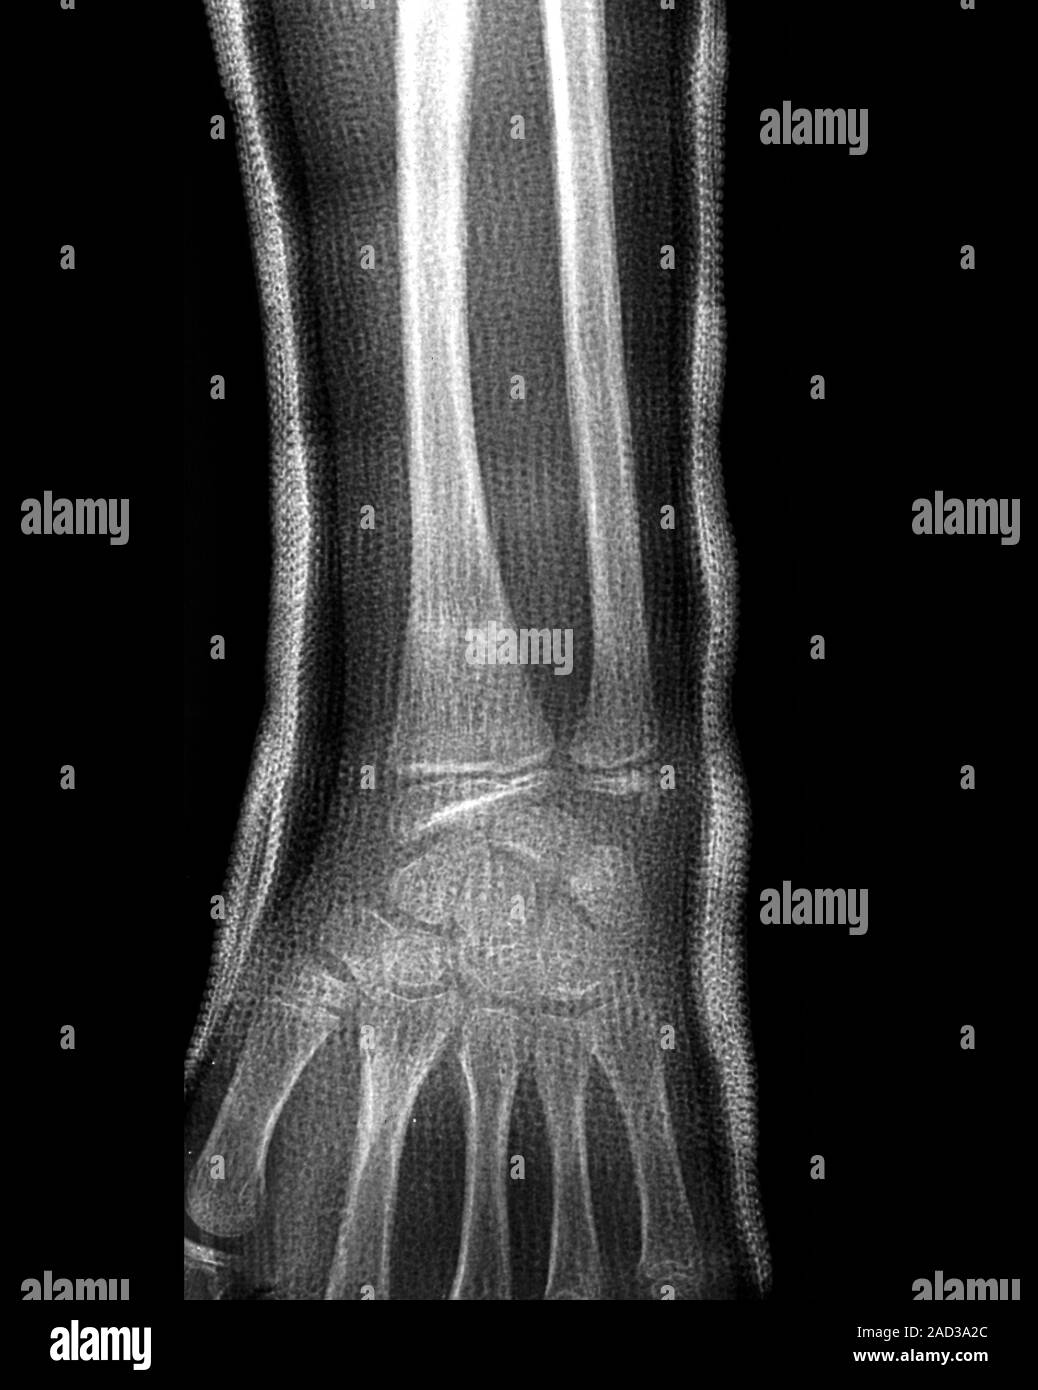

xray montrant une fracture de l'ulna et le radius Photo Stock Fracture Du Poignet Gauche Quelles sont les principales causes des fractures du poignet ? Combien de temps garder le plâtre ? les fractures du poignet localisées à l’extrémité inférieure du radius chez l’adulte sont très fréquentes. Il existe 2 types de traitement : Le poignet ne supporte pas le poids du corps et se brise. la fracture du poignet est généralement due. Fracture Du Poignet Gauche.

Fracture Du Poignet Gauche . les fractures du poignet localisées à l’extrémité inférieure du radius chez l’adulte sont très fréquentes. la fracture du poignet est généralement due à une chute sur une main tendue: cet article fait partie du dossier : Fracture du poignet chez l’adulte. les fractures du poignet sont généralement dues à une chute sur une main tendue. Quelles sont les principales causes des fractures du poignet ? Le radius se casse alors près du poignet, et l’extrémité cassée du radius est déplacée vers le Ces fractures peuvent généralement être identifiées sur des radiographies, mais une tomodensitométrie est parfois nécessaire. Combien de temps garder le plâtre ? c'est surtout l'extrémité du radius ou du scaphoïde qui se casse en cas de fracture au poignet. La plupart des fractures du poignet. Le poignet ne supporte pas le poids du corps et se brise. Il existe 2 types de traitement : douleurs et gonflement du poignet sont les symptômes les plus fréquents de la fracture du poignet. une fracture du poignet est une fracture de l’un des os de votre poignet.

Fracture Du Poignet Gauche Quelles sont les principales causes des fractures du poignet ? Combien de temps garder le plâtre ? Quelles sont les principales causes des fractures du poignet ? c'est surtout l'extrémité du radius ou du scaphoïde qui se casse en cas de fracture au poignet. une fracture du poignet est une fracture de l’un des os de votre poignet. cet article fait partie du dossier : La plupart des fractures du poignet. Ces fractures peuvent généralement être identifiées sur des radiographies, mais une tomodensitométrie est parfois nécessaire. douleurs et gonflement du poignet sont les symptômes les plus fréquents de la fracture du poignet. les fractures du poignet localisées à l’extrémité inférieure du radius chez l’adulte sont très fréquentes. Dans 50 % des cas,. la fracture du poignet est généralement due à une chute sur une main tendue: Le radius se casse alors près du poignet, et l’extrémité cassée du radius est déplacée vers le Le poignet ne supporte pas le poids du corps et se brise. Il existe 2 types de traitement : les fractures du poignet sont généralement dues à une chute sur une main tendue.